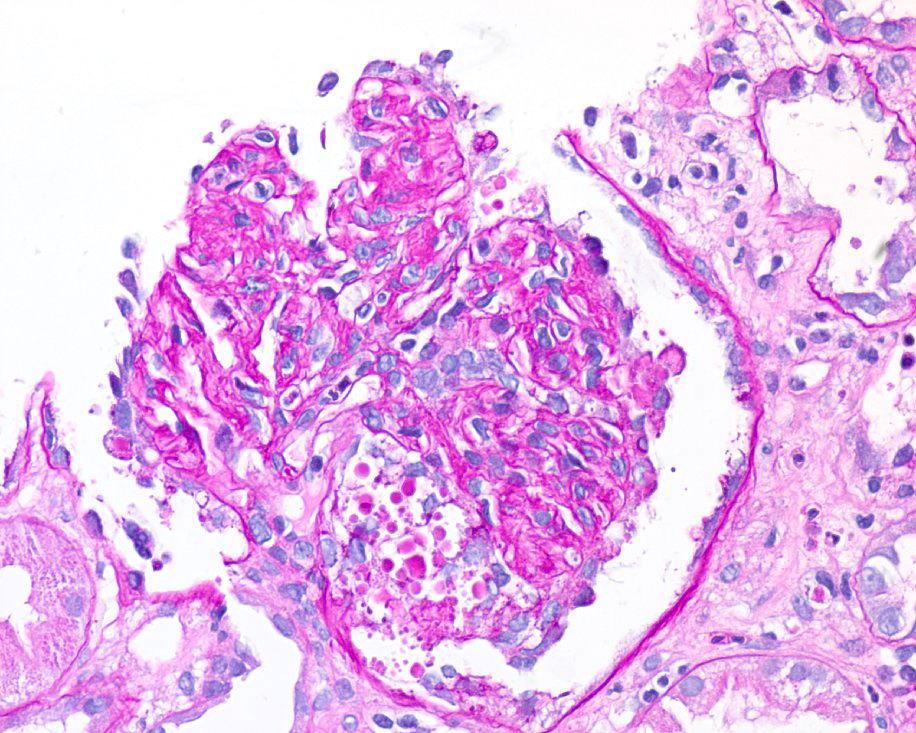

How would you describe the glomerular injury pattern seen above?

Collapsing focal segmental glomerulosclerosis (FSGS)

Strong work! We see collapse of the capillary loops as well as hypertrophy and hyperplasia of overlying podocytes outside the capillary loops. Below is a periodic acid-Schiff (PAS) slide from this patient showing the same pattern, as well as a normal glomerulus (methenamine silver stain)